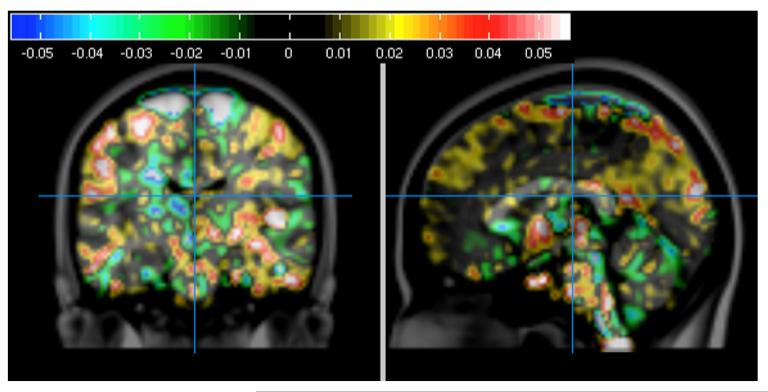

Description:On-field monitoring of head impacts, combined with finite element (FE) biomechanical simulation, allow for predictions of regional strain associated with a diagnosed concussion. However, attempts to correlate these predictions with in vivo measures of brain injury have not been published. This article reports an approach to and preliminary results from the correlation of subject-specific FE model-predicted regions of high strain associated with diagnosed concussion and diffusion tensor imaging to assess changes in white matter integrity in the corpus callosum (CC). Ten football and ice hockey players who wore instrumented helmets to record head impacts sustained during play completed high field magnetic resonance imaging preseason and within 10 days of a diagnosed concussion. The Dartmouth Subject-Specific FE Head model was used to generate regional predictions of strain and strain rate following each impact associated with concussion. Maps of change in fractional anisotropy (FA) and median diffusivity (MD) were generated for the CC of each athlete to correlate strain with change in FA and MD. Mean and maximum strain rate correlated with change in FA (Spearman ρ = 0.77, p = 0.01; 0.70, p = 0.031), and there was a similar trend for mean and maximum strain (0.56, p = 0.10; 0.6, p = 0.07), as well as for maximum strain with change in MD (-0.63, p = 0.07). Change in MD correlated with injury-to-imaging interval (ρ = -0.80, p = 0.006) but change in FA did not (ρ = 0.18, p = 0.62). These results provide preliminary confirmation that model-predicted strain and strain rate in the CC correlate with changes in indices of white matter integrity.